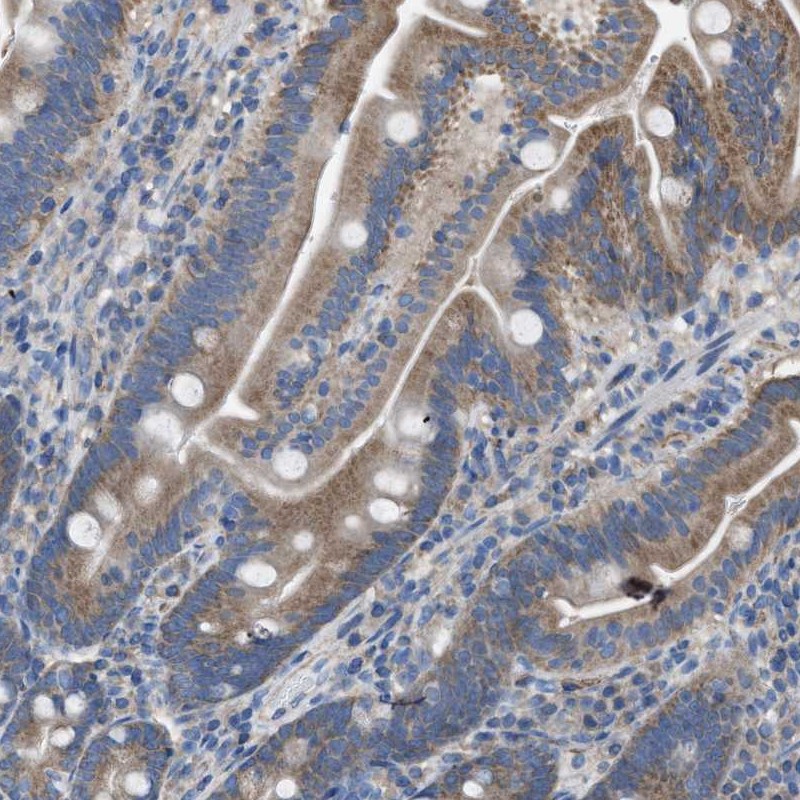

Immunohistochemical staining of human duodenum shows moderate positivity in glandular cells.